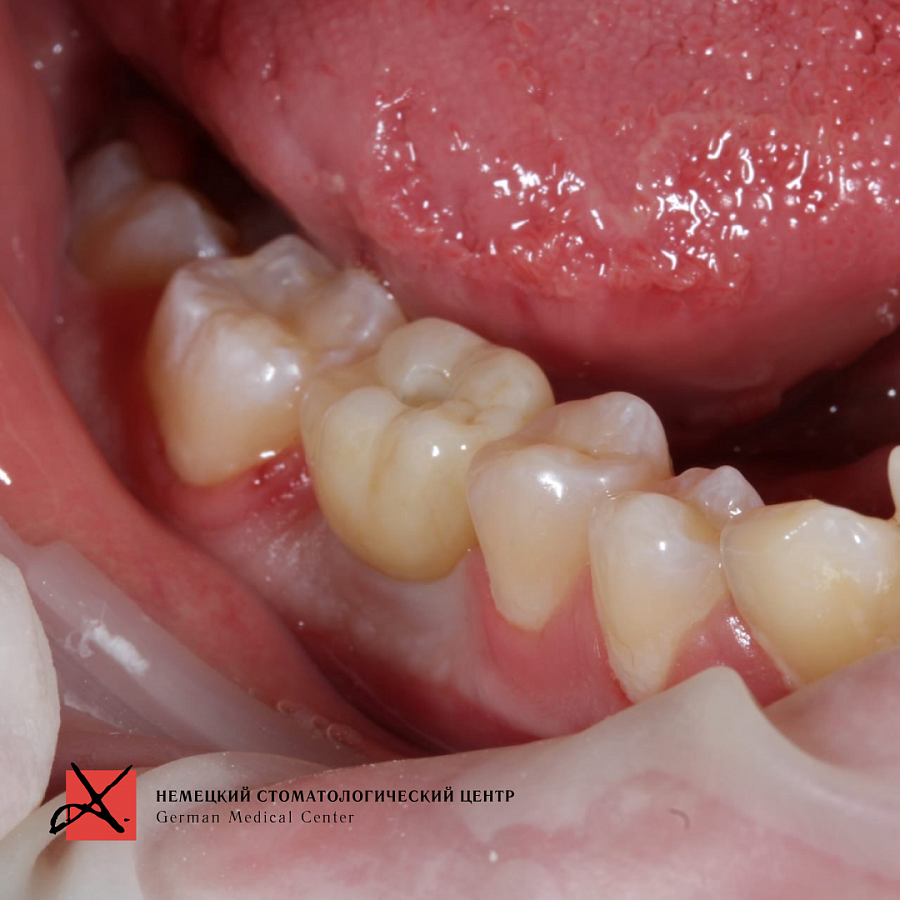

Зуб был фрагментирован, чтобы удаление прошло максимально атравматично, то есть без повреждения окружающих костных стенок. После удаления установлен имплантат. Операция прошла успешно, пациенту уже установлена зубная коронка.

Результат лечения